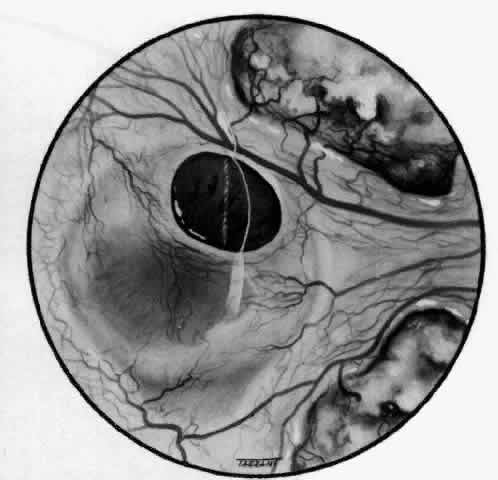

ARTERIAL PHASE Anterior Episcleral Arterial Circle The anterior ciliary arteries run radially toward the limbus within Tenon's capsule, giving few, if any, branches until they reach the anterior part of the globe. Their positions are very variable, and they do not always follow the rectus muscles. They bifurcate 2 to 5 mm behind the limbus, and each division runs forward and circumferentially to anastomose with a branch from an adjacent artery. This results in an anterior episcleral arterial circle (Figs. 3 through 5). The divisions of the anterior ciliary arteries are typically superficial at their origins but run deeper at their anastomoses. They occasionally dip too deep to be seen in fluorescein angiograms (Fig. 6).

From the anterior episcleral arterial circle, four distinct circulations are supplied: episcleral, anterior conjunctival, limbal, and iris. Episcleral Circulation Immediately after their origin by bifurcation of the anterior ciliary arteries, the contributions to the anterior episcleral circle divide again to give recurrent branches that run posteriorly and subdivide to form a netlike episcleral plexus (see Fig. 5; Fig.7). The variability of the positioning of the anterior ciliary arteries inevitably leaves large areas of episclera far from such an arterial supply (see Figs. 4, 6, and 7). These areas receive other posterior branches from the episcleral circle. Where the circle runs deep within the sclera, such branches appear as isolated perforating vessels (see Fig. 6). They fill very shortly after the episcleral circle, and they also divide repeatedly as they run posteriorly.

Anterior Conjunctival Circulation Throughout their superficial course, the arteries of the episcleral circle give off fine loops that run forward into the limbal reflection of the conjunctiva before curving back radially and dividing to form the lacework of the anterior conjunctival capillary plexus (see Fig. 2). The delicate column of blood within the anterior conjunctival loops may be punctuated by a string of individual erythrocytes, suggesting that the lumen is approximately 12 μm in diameter. Anterior conjunctival loops may also arise from perforating posterior branches of the episcleral circle (see Fig. 6). The anterior conjunctival circulation, supplied by the anterior ciliary arteries, always fills before the posterior conjunctival circulation, which is derived from the posterior tarsal vessels (see Figs. 4 and 5). The watershed zone between these sources can fill very late (see Fig. 5). However, anterior conjunctival loops do sometimes anastomose with arteries of similar caliber derived from the posterior tarsal circulation. Limbal Arcades Limbal arcades are supplied by anterior branches from the episcleral circle. Their origins are often shared with those of the anterior conjunctival loops, and, where the circle runs deep, they too are derived from the perforating posterior branches. They often fill very late during a normal angiogram (see Fig. 7). The limbal capillary loops never leak fluorescein, even during high-dose angiograms, suggesting that their endothelial cells are united by tight junctions. Iris Vessels The first flush of fluorescein within the anterior episcleral arterial circle always coincides with filling of the radial arterioles of the iris. It may be implied from this that the iris receives a major supply from the anterior ciliary circulation (see Fig. 6). In some angiograms, the iris circulation appears to derive directly from the episcleral circle. This raises the possibility that the “major circle of the iris” and the episcleral arterial circle are less distinct entities than has hitherto been presumed. VENOUS PHASE Anterior ciliary veins accompany the arteries, but there is no well-organized venous ring corresponding to the anterior episcleral arterial circle. The posterior episcleral branches of the arterial circle are paralleled by centripetal venules, and looping anterior conjunctival venules are interspersed between the arterioles (see Figs. 4 and 5). The posterior conjunctiva drains back into the tarsal circulation. CAPILLARY PHASE The episcleral capillary net is often difficult to discern below the more prominent conjunctival circulation. It is most clearly seen when the conjunctival circulation fills late for anatomic or pathologic reasons. The anterior conjunctival capillary plexus forms an interlacing network between the anterior conjunctival arterioles. Perfusion of the watershed zone that separates the territories supplied by the anterior ciliary and posterior tarsal systems may be delayed by as much as 15 seconds after first flush (see Figs. 5 and 7). However, this region is often crossed by arteriolar anastomoses between the two circulations, and the destination of venous blood is irrespective of its origin from the anterior ciliary or posterior tarsal circulations. |